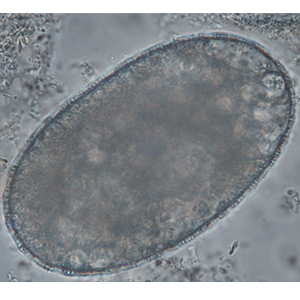

Les œufs de strongle présentent globalement la même morphologie ; ce sont des œufs ovalaires, à paroi lisse, possédant une morula et des faces latérales non parallèles. Leur taille est très variable (40 x 60 μm à 110 x 230 μm) et les groupes évoqués ci-dessus peuvent présenter des caractéristiques permettant d’orienter le diagnostic mais ces dernières sont à prendre avec précaution. Ces œufs, lorsqu’ils persistent longtemps dans le milieu extérieur, peuvent présenter un embryon vermiforme (Garcia, 2021).

- Les nématodes libres de l’environnement :les œufs de nématodes libres de l’environnement sont en général plus gros que les strongles (70 à 120 μm de longueur pour 24 à 43 μm de largeur). Ils peuvent posséder des éléments caractéristiques (globules réfringents chez Heterodera radicicola). En cas de doute, il est recommandé d’avoir recours à des techniques de coproculture ou de Baermann.

- Les anguillules(Strongyloides): ces nématodes rentrent dans le diagnostic différentiel des œufs de strongle embryonnés. A l’inverse des œufs de strongles, ils mesurent 40-70 μm de longueur pour 20-35 μm de largeur, possèdent une paroi très fine et leurs faces latérales sont parallèles (Garcia, 2021).

- Les acariens: les œufs d’acarien sont plus gros que la plupart des œufs de strongles (100-140 μm de longueur pour 50-80 μm), ils présentent également un contenu granuleux, avec de nombreuses vacuoles nutritives. Lorsque l’embryon est développé, il prend une forme caractéristique d’acarien (Petithory et al., 1995).

- Les trachéides: certaines cellules végétales peuvent prendre des dimensions proches de celles des œufs de strongle. Elles peuvent être remplies de matériel granuleux et mimer la forme de ces derniers. La paroi est néanmoins plus épaisse et la forme plus anguleuse (Petithory et al., 1995).